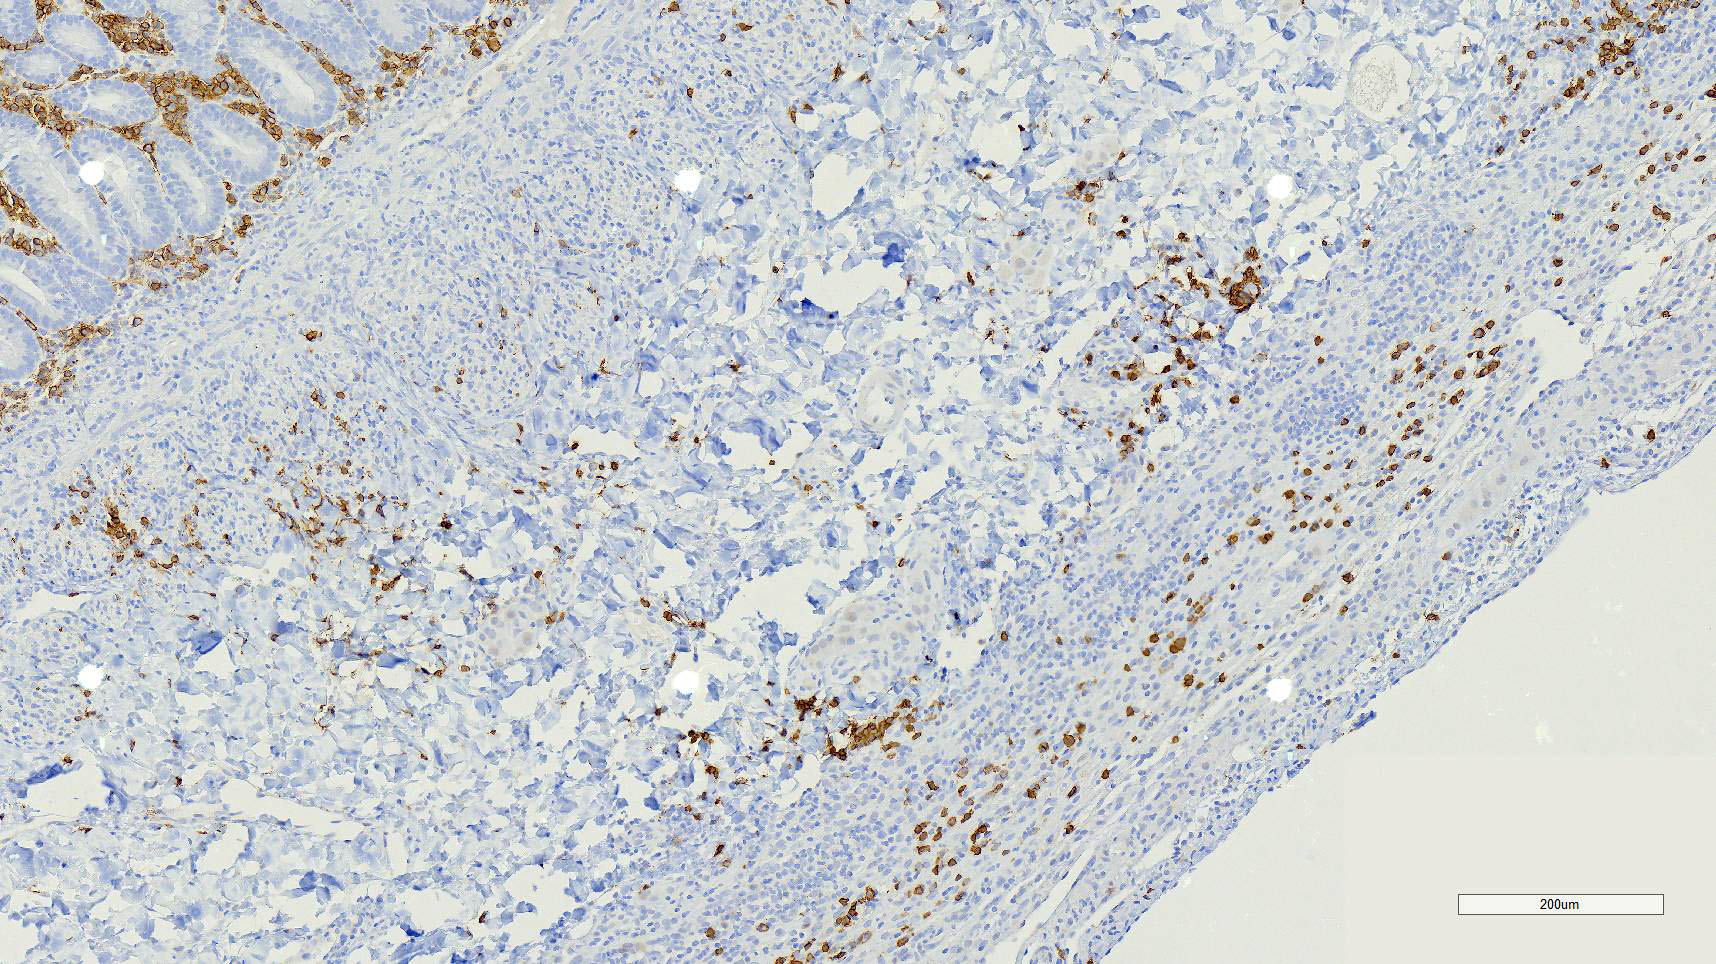

Duodenum, jejunum and ileum: Diffusely throughout the sections, there is partial to complete loss of the leiomyocytes of the outer and inner muscularis, which are multifocally replaced by loose fibrous connective tissue (fibrosis). The remaining smooth muscle is infiltrated by large numbers small and intermediate lymphocytes, few macrophages and neutrophils. The same inflammatory infiltrate is present throughout the muscularis mucosae. Remaining leiomyocytes have pale, frequently vacuolated cytoplasm. In the submucosa, muscularis and serosa there are small to moderate numbers of perivascular lymphocytes. Small lymphocytes, and infrequently neutrophils, surround or infiltrate the myenteric and submucosal ganglia, though neurons do not exhibit degenerative changes. The lamina propria contains a markedly increased number of lymphocytes, plasma cells and a mildly increased number of eosinophils. The epithelium is diffusely overlain by myriad bacterial rods. The serosa is mildly expanded by increased clear space (edema) and is lined multifocally by markedly hypertophied mesothelium. In the stomach a similar process is observed but restricted to the outer aspect of the muscularis with a patchy/multifocal distribution and sparing of the muscularis mucosae. (section not submitted).

Microscopic findings reported for this condition consist of mild to marked mononuclear infiltrate, myofiber degeneration and fibroplasia or fibrosis centered within the muscularis propria of the stomach, small and large intestinal wall with the jejunum being the most severely and chronically affected segment.7,15 In early lesions the inflammation and smooth muscle degeneration are segmental, random between the outer and inner muscularis layers and sparing of the muscularis mucosae.15 Concurrent cecal involvement leading to impaction has also been described.5 Consistent histologic findings included T-lymphocyte inflammation within the muscularis propria with relative sparing of the mucosa, submucosa and neural plexuses.14 In one case report the inflammatory infiltrate was predominantly of B-lymphocytes and featured extensive angiogenesis.6 Leiomyocytes appear to be the target of the inflammation given the presence of various stages of degeneration leading to complete myofiber loss in chronic stages of the disease. Superficial inflammation is a frequent secondary finding in CIPO and has been associated with bacterial overgrowth, which were changes observed in this case.6 Neuropathy has not been a feature in most reports of canine CIPO. Inflammatory cells obscuring the myenteric and submucosal plexuses in this case were considered an extension from the neighboring inflammation as no degenerative changes were observed in the neurons. Myenteric ganglionitis has, however, been reported occurring concurrently with leiomyositis.10

The pathogenesis for this condition remains unclear, though the targeting of smooth muscle by T-lymphocytes is supportive of a cell-mediated inflammatory process suggestive of an immune-mediated process against intestinal smooth muscle.11,14,15 In humans with intestinal leiomyositis, the inflammation is specific for the intestinal musculature as leiomyocytes of vessels or other tissues are unaffected.15 Humans with intestinal leiomyositis can have autoimmune disease as a preexisting condition, including systemic lupus erythematosus, rheumatoid arthritis, scleroderma, and autoimmune hepatitis.7 Neither the dog in this case nor those in the largest case series in dogs with leiomyositis had concurrent evidence of systemic autoimmune disease.14 In few human cases, acute episodes of infectious gastroenteritis or diarrhea preceded the development of gastrointestinal distention.7 Molecular mimicry has been proposed as a mechanism for the development of leiomyositis, although an explanation of restriction of the inflammation to the gastrointestinal tract was not elucidated.7

Yet again, a fantastically written comment by the contributor that hits on the majority of conference discussion points! Chronic intestinal pseudo-obstruction (CIPO) has also been known by many names throughout its history, including fibrosing gastrointestinal leiomyositis, intestinal leiomyositis, idiopathic intestinal pseudo-obstruction, chronic intestinal dysmotility, and enteric myopathy. Many of these names are no longer in use, but intestinal leiomyositis and CIPO are most commonly utilized in the current literature. A good way to think about CIPO is that it is the clinical disease that can result from intestinal leiomyositis. This entity was last seen in the WSC in 2017 during Conference 4, Case 2. Histologically, the focus of lymphocytic inflammation on the smooth muscle cells of the intestine with replacement fibrosis and an absence of infectious organisms should make one think about this clinical syndrome, especially if the history fits.